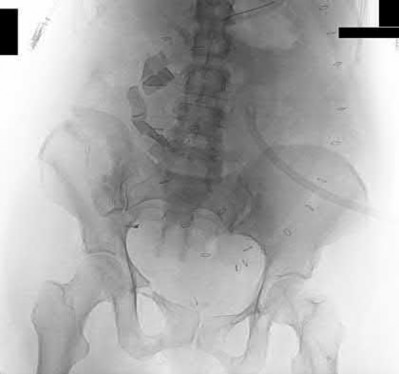

The image shows a reverse obliquity intertrochanteric hip fracture.

According to the referenced article by Haidukewych et al, unstable peritrochanteric hip fractures have a worse outcome (failed in 9/16 cases) if treated with a sliding hip screw. Two additional factors that were found to have a strong correlation with postoperative failure (nonunion, loss of reduction) were poor reduction and poor implant placement. In this study, fixed angle devices were superior. Intramedullary fixation has the added advantage of a shorter lever arm and less potential for fracture collapse and limb shortening.

The IMN also acts as a medial buttress.

According to Sanders et al, the dynamic condylar screw (DCS) can also be used in subtrochanteric models, but should not be used if extensive comminution is seen, as they reported a high failure rate with DCS in these fractures if highly comminuted. They report a 77% overall union rate with this device.